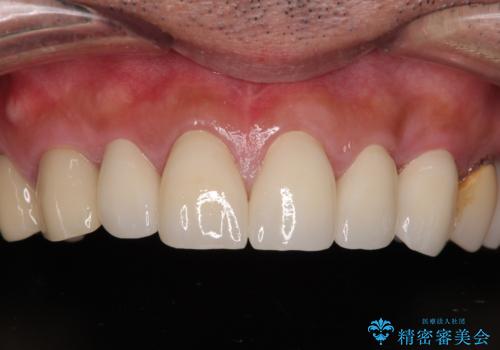

右上側切歯に対して根管治療を行い、その後右上側切歯から左上犬歯まで計5本をオールセラミッククラウンで補綴する治療計画をご提案しました。

前歯の詰め物や被せ物の見た目が気になる

過去の治療跡をきれいにやり直したい

自然で美しい前歯にしたい

オールセラミック治療を検討している